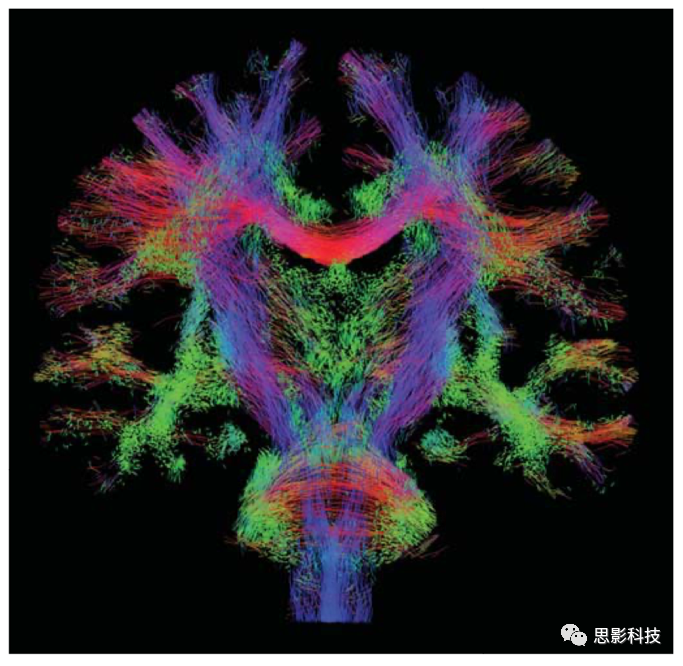

1.確定性纖維追蹤    確定性纖維追蹤主要使用FACT、steamline等追蹤方法根據張量主方向以及預設的偏轉角閾值、FA閾值等參數對全腦纖維束進行構建,而后通過設定ROI的方式追蹤特定纖維束,并計算纖維束的數目、平均FA等相關指標。

圖例:全腦纖維束構建